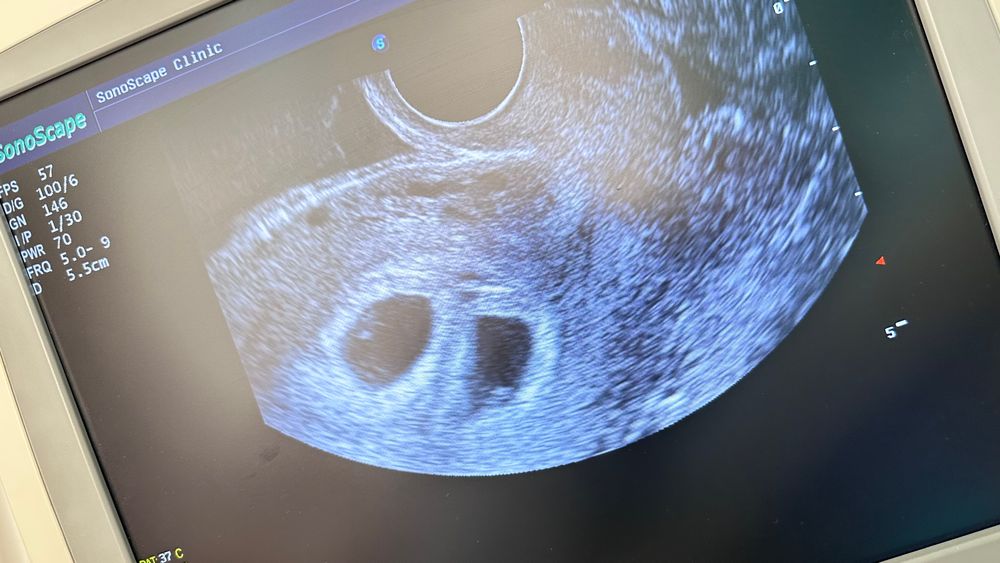

Я БЕРЕМЕННА !Доброе утро девочки! (Хотя конечно еще ночь-сон сбит🤦🏻♀️ напрочь). Была я вчера на узи… в общем та-даааам: 2е малышей!!! Не поделились-все ок… Ато многие писали, что хгч мой похож на тройной. Я и сама , конечно, переживала, но напрасно. По сроку от М вчера было 5 нед и 4 дня, а вот ребята на 6 нед-так Ре сказала. Отправила становиться на учет. Сердечки уже у обоих мерцают, ктр 1-1,97; 2-3.05…